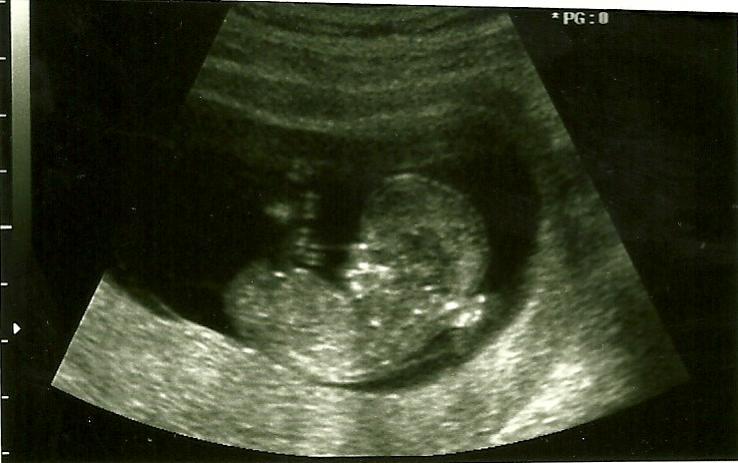

Do you see a nub? 12w2d

I went in for an u's today and babe is measuring 12w2d. I was intently focused on the nub area but didn't see a thing! I have three pics, but I still don't see a nub in any of them. Attachment 154Attachment 155Attachment 156Does anyone see anything that would lead them one direction or another? TIA!

and . . ? girl or boy nub? is there a nub in the second one?